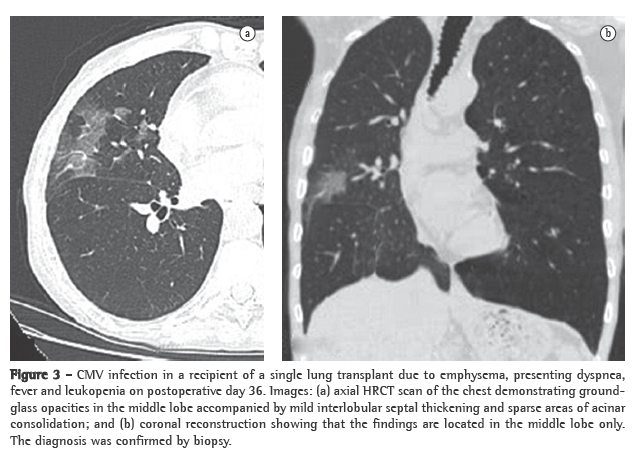

Opportunistic infection occurs in 34-59% of lung transplant recipients.(13) Unfortunately, in patients with new opportunistic pneumonia, chest X-ray findings can be normal, and abnormal findings, when present, are often nonspecific.(11) Cytomegalovirus (CMV) is the most common opportunistic infection among such patients.(14) The incidence of CMV infection peaks between 1 and 2 months after transplantation, most cases occurring between postoperative months 1 and 12.(11,14) Infection with CMV can be primary and secondary. Primary infection occurs in over 90% of CMV seronegative patients receiving a CMV seropositive donor lung and becomes severe in 50-60% of such cases.(11) Secondary infection results from exposure to a different CMV strain or from reactivation of a latent infection in the recipient and is usually less severe than is primary infection.(11) Clinical manifestations of CMV infection include dyspnea, fever, malaise and leukopenia, although many patients with histologically proven CMV pneumonia are asymptomatic.(15) A diagnosis of CMV pneumonia is typically confirmed only after bronchoalveolar lavage and transbronchial biopsy. The radiologic manifestations of CMV pneumonia include, as shown in Figure 3, ground-glass opacities, interlobular septal thickening and consolidation, as well as diffuse reticular or reticulonodular opacities, nodules and small areas of effusion.(14) In lung transplant recipients with active CMV infection, chest X-ray findings can be normal,(11) CT scans better depicting the radiological manifestations of the infection, which almost exclusively affects the allograft. The most common CT manifestations are ground-glass opacities, tree-in-bud opacities, airspace consolidation, nodules, interlobular septal thickening, pleural effusions, thickened/enlarged pleura and bronchiectasis.(11-15) Other common viral pulmonary pathogens affecting this population include herpes simplex virus, adenovirus and respiratory syncytial virus.(11)